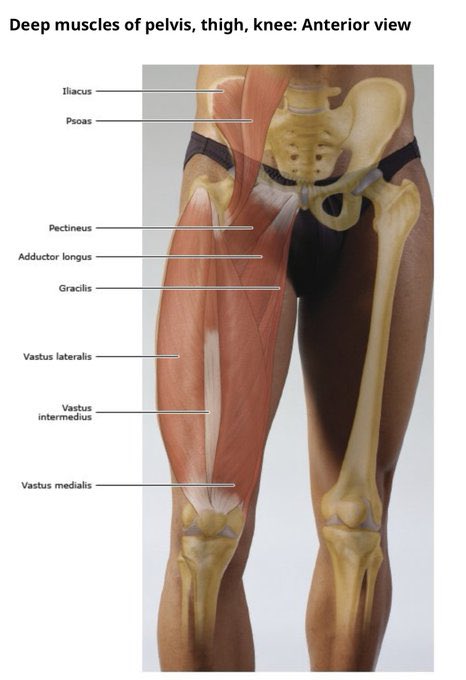

🔸דירוג הפציעה(לפי מיקום וחומרת הקרע): רוב פציעות המפשעה הן פציעות המשקפות עומס ויתרחשו בשריר ה- Adductor Longus באיזור המעבר בין סיבי שריר לגיד. דרגה1- קרע חלקי ומצומצם שמסב כאב אך ללא ירידה בכח/בתנועה. דרגה2- קרע חלקי עם כאב, נפיחות וגם הפרעה ביציבות ובתנועה. דרגה3- קרע מלא

🔸שריר המפשעה(המקרבים) הוא למעשה מקלעת שרירים(שישה לשם הדיוק). הם מחברים את עצם האגן לירך, ממוקמים בין ההמסטרינג האחורי לארבע ראשי הקדמי, ומשתתפים בכלל תנועות מפרק הירך ובעיקר מבצעים את תנועת הצמדת הירך מהחוץ בחזרה פנימה אל קו האמצע. בכדורגל החשיבות המרכזית היא בייצוב שתי הרגליים